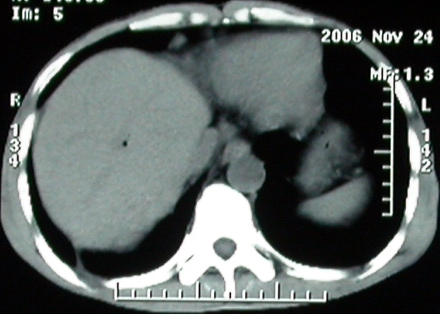

标题: CT5432:上腹隐痛、饱胀、消瘦2-月(尾状叶肝癌)。 [打印本页]

标题: CT5432:上腹隐痛、饱胀、消瘦2-月(尾状叶肝癌)。

男,57岁。

平扫

手术结果:

肝脏尾状叶肝癌(沿肝十二指肠韧带向下韧带内生长,门腔间隙外压增大),大结节性肝硬化,胆囊积脓,胆道感染。术中见肝外胆道2cm直径,肿瘤向前压迫胆管至扁平状态。